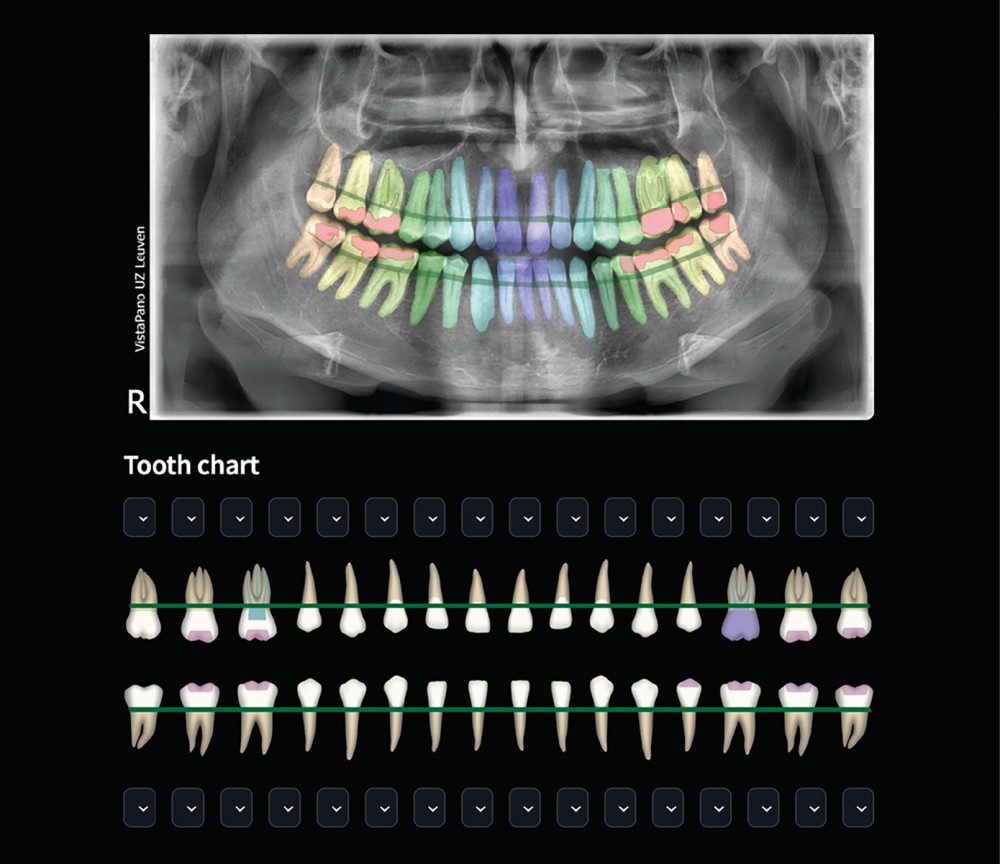

Si l’IA envahit discrètement notre quotidien et que nous, êtres humains, lui faisons de plus en plus confiance, dans la pratique dentaire, nous semblons exprimer plus souvent une certaine méfiance à son égard [1]. Cette méfiance est tout à fait compréhensible, car nos tâches diagnostiques et nos traitements quotidiens exigent un haut degré de précision. En tant que cliniciens, nous ne voulons pas compromettre la qualité des soins prodigués en utilisant l’IA. Cependant, cette dernière peut également être développée sur la base d’un apprentissage supervisé de haut niveau, grâce à une interaction quasi continue et parfaite entre des ingénieurs en IA hautement qualifiés et des dentistes spécialisés. Cette interaction et ces retours d’information sont indispensables pour fournir des renseignements pertinents, non seulement pour le développement de l’IA, mais également pour toute formation complémentaire, validation et résultat clinique [1]. L’IA peut ainsi devenir l’assistant parfait, capable de travailler beaucoup plus rapidement et de manière plus cohérente que le praticien, sans sacrifier la précision [2, 3] (fig. 1). Cependant, l’IA doit être surveillée tout au long de son cycle de vie et apprendre de ses erreurs en étant continuellement soumise à la supervision d’un expert humain à toutes les phases de développement, de validation et de maintenance, avec un retour d’information sur les résultats incorrects renvoyé directement à l’outil d’IA basé sur le cloud. Ce n’est qu’ainsi que l’IA dentaire pourra devenir l’assistant du futur.